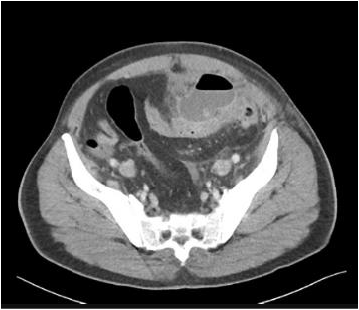

Paciente, 58 anos, chega ao pronto atendimento com história de dor em fossa ilíaca esquerda, que piorou progressivamente nas últimas 48 horas, sem febre. O exame físico mostrou abdome pouco distendido, doloroso à palpação difusa, dor à palpação mais localizada em fossa ilíaca esquerda, onde o sinal de Blumberg apresenta-se positivo.

O hemograma mostra contagem de leucócitos de 13.500/mm3 com 867 bastões, e a dosagem do PCR foi de 23 mg%. Foi solicitada a TC de abdome mostrada abaixo.

Fonte: https://doi.org/10.53347/ID.52993

Acesso em abril 2022

Em relação ao caso, é correto afirmar que: